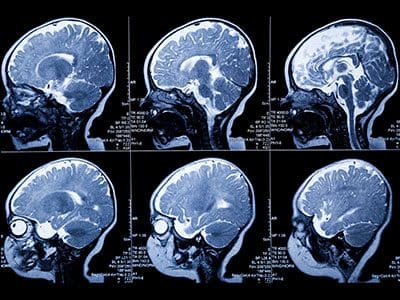

Brain MRI scans showing multiple cross-sections.

In a study published in the journal Cerebral Cortex, Developing Brain Institute researchers led by Kevin M. Cook, Ph.D., used fetal MRI to examine the association between neighborhood conditions and fetal brain growth during pregnancy.